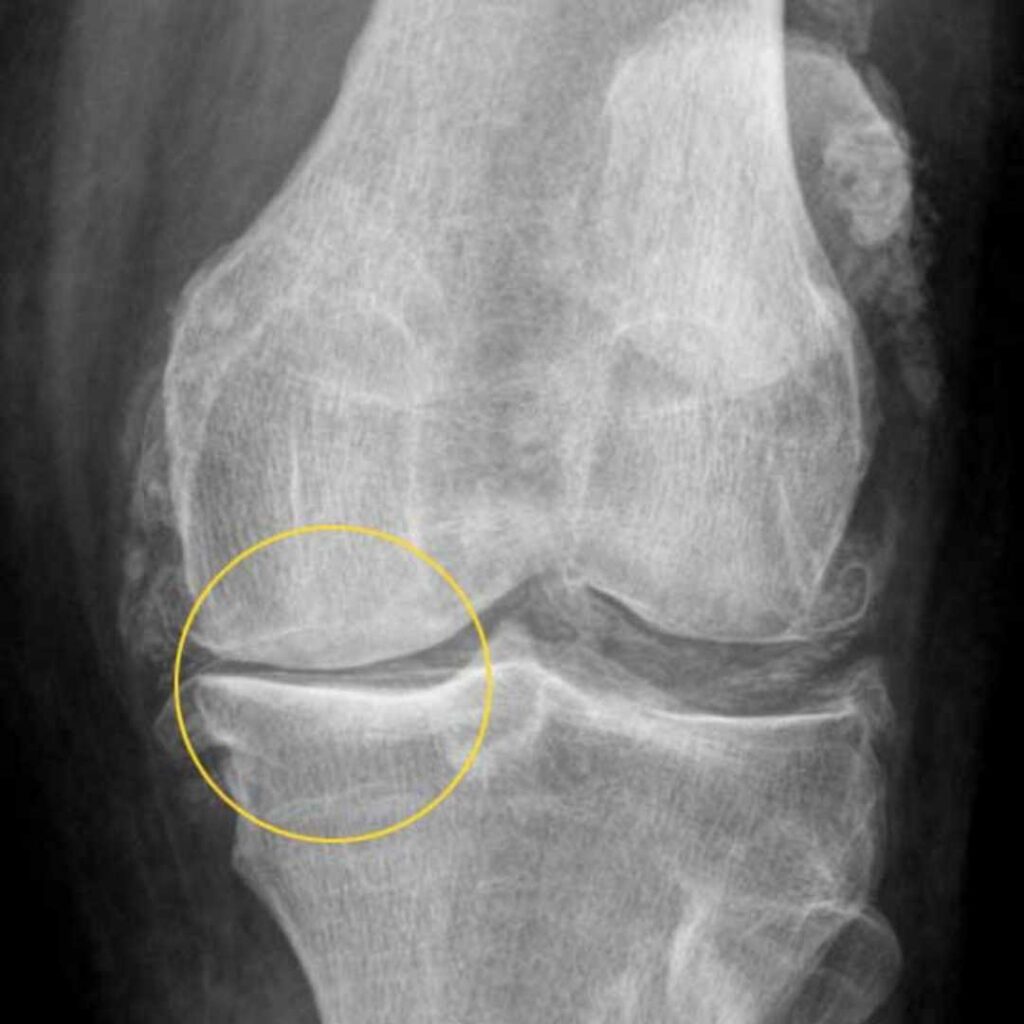

« Le résultat de l’IRM a été un choc »

« Lorsque j’ai eu les résultats de l’IRM entre les mains, j’ai été choquée. Le médecin a dit mot pour mot Madame Tissot, votre cartilage a pratiquement disparu. Seule une opération peut vous aider’. J’étais complètement sous le choc.

« Il regarde mes images IRM, acquiesce – puis dit Madame Tissot votre cartilage est effectivement très endommagé. Mais vous savez quoi ? Ce n’est pas le vrai problème.’